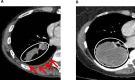

Introduction: Recurrence rate following radical therapy for lung cancer remains high, potentially reflecting occult metastatic disease, and better staging tools are required. Minimal pleural effusion (mini-PE) is associated with particularly high recurrence risk and is defined as an ipsilateral pleural collection (<1/3 hemithorax on chest radiograph), which is either too small to safely aspirate fluid for cytology using a needle, or from which fluid cytology is negative. Thoracoscopy (local anaesthetic thoracoscopy (LAT) or video-assisted thoracoscopic surgery (VATS)) is the gold-standard diagnostic test for pleural malignancy in patients with larger symptomatic effusions. Staging by Thoracoscopy in potentially radically treatable Lung Cancer associated with Minimal Pleural Effusion (STRATIFY) will prospectively evaluate thoracoscopic staging in lung cancer associated-mini-PE for the first time.

Methods and analysis: STRATIFY is a prospective multicentre observational study. Recruitment opened in January 2020. The primary objective is to determine the prevalence of detectable occult pleural metastases (OPM). Secondary objectives include assessment of technical feasibility and safety, and the impact of thoracoscopy results on treatment plans, overall survival and recurrence free survival. Inclusion criteria are (1) suspected/confirmed stages I-III lung cancer, (2) mini-PE, (3) Performance Status 0-2 (4), radical treatment feasible if OPM excluded, (5) ≥16 years old and (6) informed consent. Exclusion criteria are any metastatic disease or contraindication to the chosen thoracoscopy method (LAT/VATS). All patients have LAT or VATS within 7 (±5) days of registration, with results returned to lung cancer teams for treatment planning. Following an interim analysis, the sample size was reduced from 96 to 50, based on a lower-than-expected OPM rate. An MRI substudy was removed in November 2022 due to pandemic-related site setup/recruitment delays. These also necessitated a no-cost recruitment extension until October 2023.